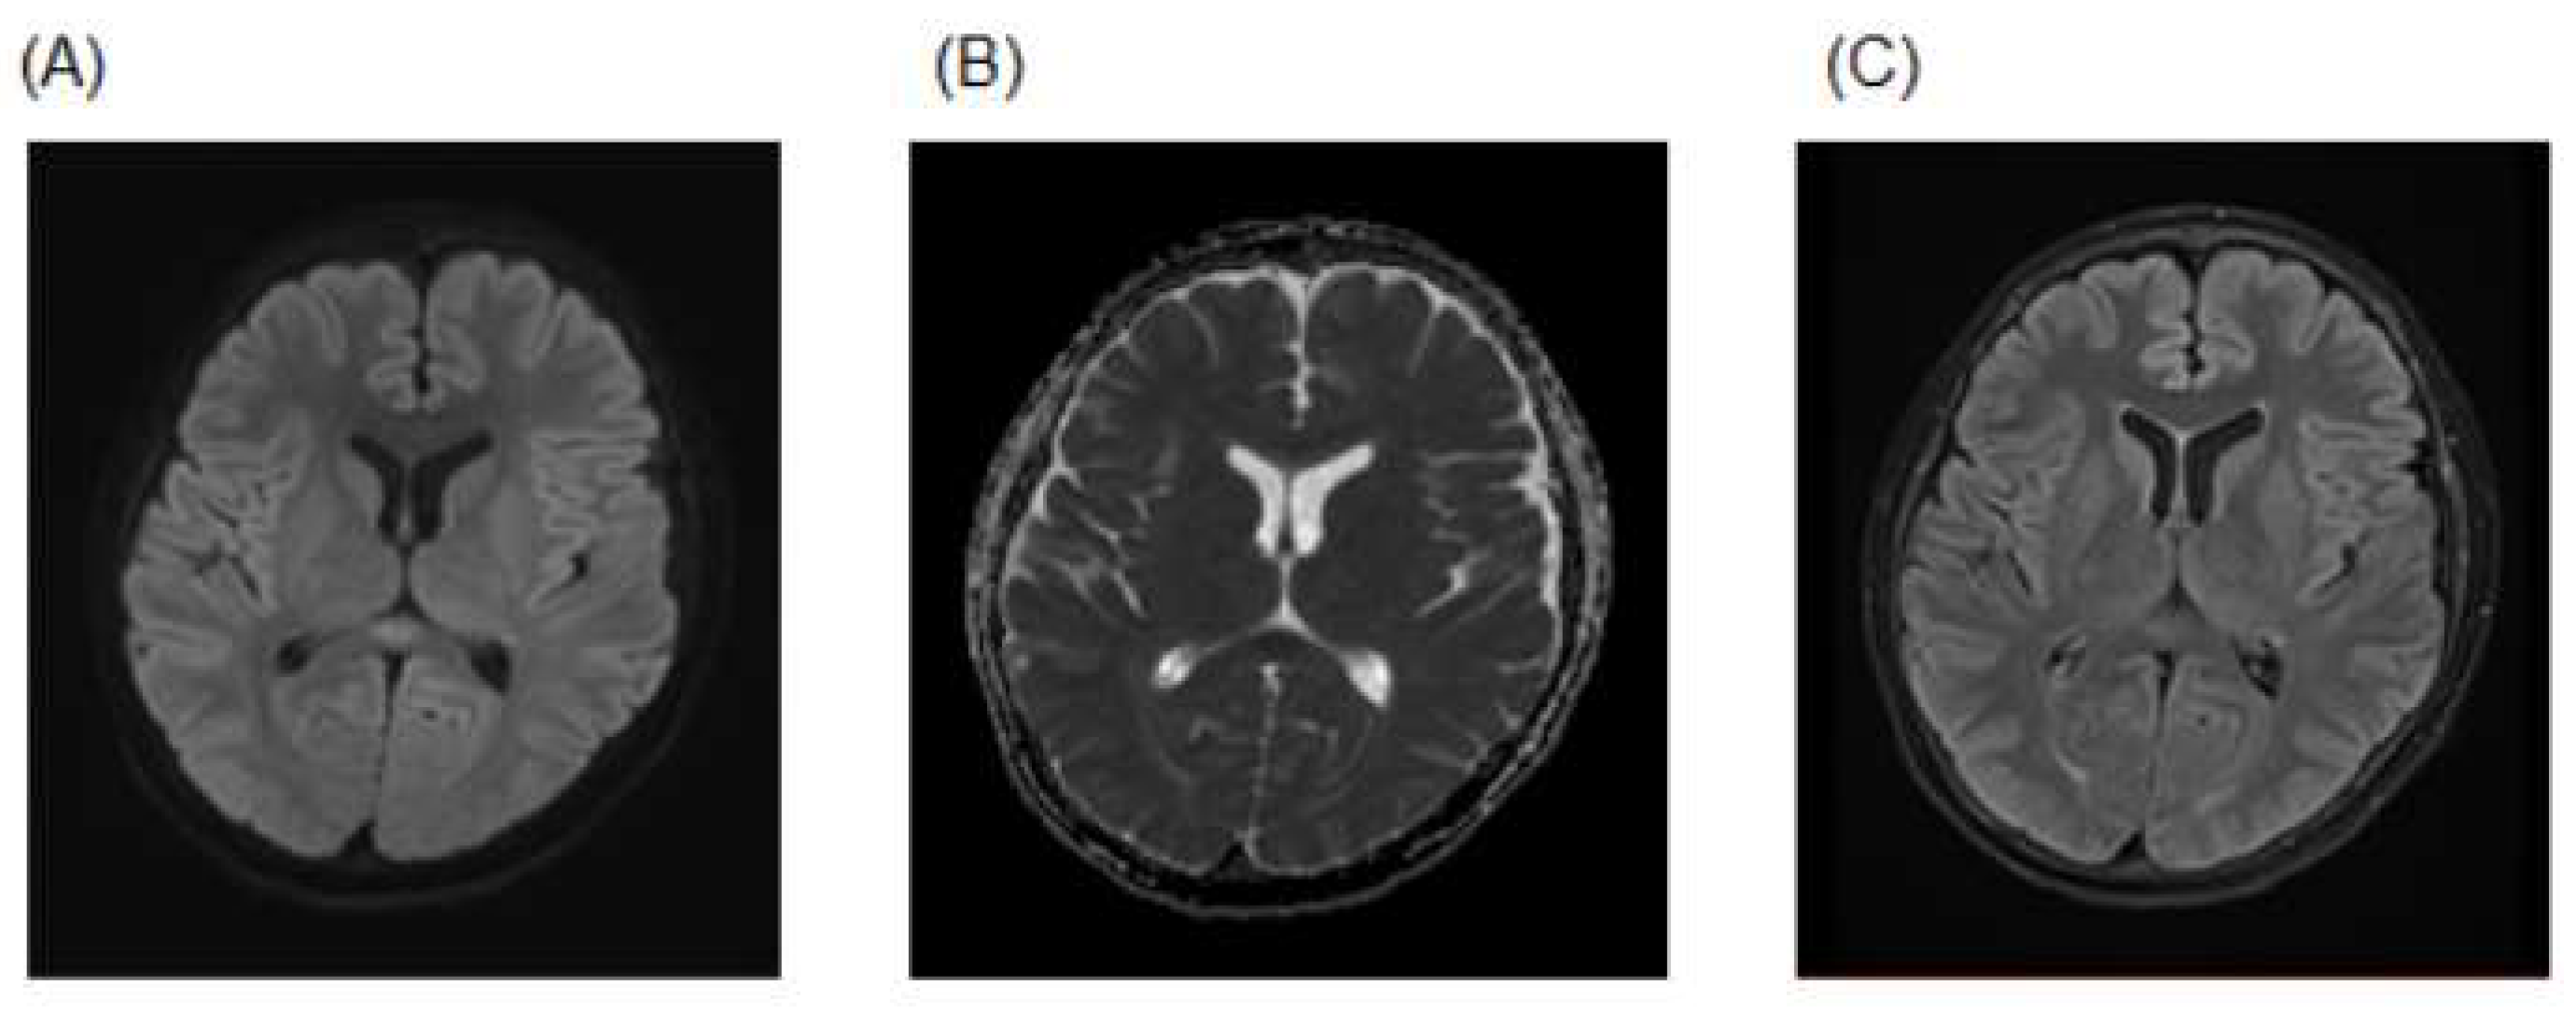

Upon presentation, his oxygen saturation was 99% on room air. A neurological examination revealed altered sensorium with disorientation; otherwise, there were no focal neurologic deficits or meningeal signs. The other findings of the physical examination were normal. Laboratory exams showed normal leukocyte and platelet counts, decreased serum sodium (128.9 mEq/L), decreased serum chloride (90 mEq/L) decreased plasma osmolality (266.9 mOsm/L) and elevated C-reactive protein (13.68 mg/dL). Thoracic computed tomography (CT) showed multiple ground glass opacities and consolidation throughout both lungs. Brain magnetic resonance imaging (MRI) showed an oval high-signal area in the midline of the corpus callosum from diffusion-weighted imaging (DWI), and a low apparent diffusion coefficient (ADC) value on the ADC map in the same area. The fluid-attenuated inversion recovery (FLAIR) sequence showed hyperintense lesions in the same area (Figure 1). A cerebrospinal fluid (CSF) examination revealed a normal glucose level (serum glucose level 126 mg/dL), chemistry and cell count. A BIOFIRE FILMARRAY Meningitis/Encephalitis (ME) Panel (BioFire Diagnostics, Salt Lake City, UT, USA) was negative.

Figure 1.

(A) Brain MRI on admission showing an oval high-signal area in the midline of the corpus callosum with diffusion-weighted imaging (DWI). (B) Apparent diffusion coefficient (ADC) value on ADC map in the same area was low. (C) Fluid-attenuated inversion recovery (FLAIR) sequence showed hyperintense lesions in the same area.